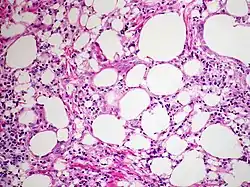

The gross appearance of a lipid pneumonia is that in which there is an ill-defined, pale yellow area on the lung. This yellow appearance explains the colloquial term "golden" pneumonia.[7]

At the microscopic scale foamy macrophages and giant cells are seen in the airways, and the inflammatory response is visible in the parenchyma.